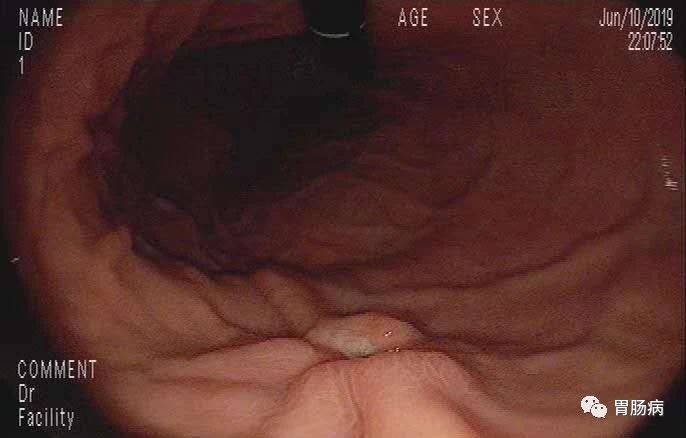

首先发现胃窦黏膜呈鸡皮样隆起,经验告诉我:胃窦、胃体黏膜呈结节状表现,叫做鸟肌样胃炎或鸡皮样胃炎,它大多与Hp感染有关,清除Hp后结节性胃炎可减轻或消失,但是有发生未分化癌的可能。

充分充气后,胃腔皱襞完全展开,果然在胃体中部大弯侧近前壁发现一处隆起凹陷型溃疡病变,大小约2x1.5cm,看起来,这就不是什么好东西!

于是在病灶处深部取材8块送检。

数天后,活检结果出来了:低分化印戒细胞癌!